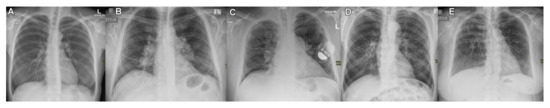

4.2. Chest Radiograph in Two Projections and Staging by Scadding

| Scadding stage | |

| 0 | 0 |

| 1 | 9 |

| 2 | 63 |

| 3 | 6 |

| 4 | 1 |

| Scadding Stages | 0 | 1 | 2 | 3 | 4 |

|---|---|---|---|---|---|

| CXR findings | Normal | Hilar or mediastinal nodal enlargement | Hilar or mediastinal nodal enlargement and parenchymal disease | Parenchymal disease only | Lung fibrosis and volume loss |

| Number of patients | 0 | 9 | 63 | 6 | 1 |